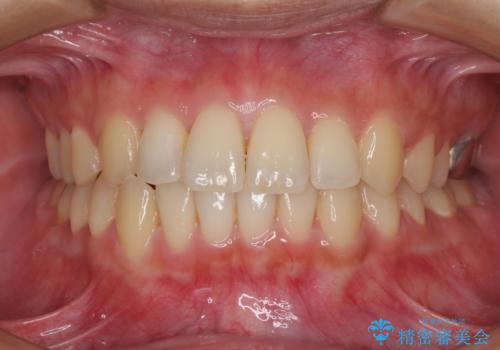

治療期間が世界的な感染症の流行時期と重なったため、海外と日本での往来が困難となり、治療継続が懸念されました。

それでも、しっかりとマウスピースを装着してくださったので、大きなトラブルもなく治療を終えることができました。